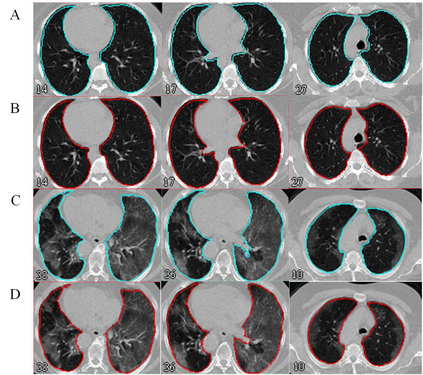

Automated semantic image segmentation is an essential step in quantitative image analysis and disease diagnosis. This study investigates the performance of a deep learning-based model for lung segmentation from CT images for normal and COVID-19 patients. Chest CT images and corresponding lung masks of 1200 confirmed COVID-19 cases were used for training a residual neural network. The reference lung masks were generated through semi-automated/manual segmentation of the CT images. The performance of the model was evaluated on two distinct external test datasets including 120 normal and COVID-19 subjects, and the results of these groups were compared to each other. Different evaluation metrics such as dice coefficient (DSC), mean absolute error (MAE), relative mean HU difference, and relative volume difference were calculated to assess the accuracy of the predicted lung masks. The proposed deep learning method achieved DSC of 0.980 and 0.971 for normal and COVID-19 subjects, respectively, demonstrating significant overlap between predicted and reference lung masks. Moreover, MAEs of 0.037 HU and 0.061 HU, relative mean HU difference of -2.679% and -4.403%, and relative volume difference of 2.405% and 5.928% were obtained for normal and COVID-19 subjects, respectively. The comparable performance in lung segmentation of the normal and COVID-19 patients indicates the accuracy of the model for the identification of the lung tissue in the presence of the COVID-19 induced infections (though slightly better performance was observed for normal patients). The promising results achieved by the proposed deep learning-based model demonstrated its reliability in COVID-19 lung segmentation. This prerequisite step would lead to a more efficient and robust pneumonia lesion analysis.